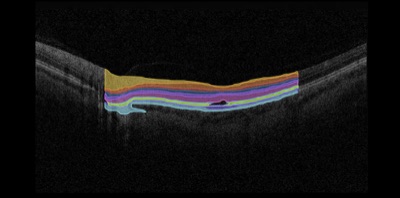

OD Fundus

OCT Macula Over a decade of partnership with the eye care community. Preserving 25+ years of clinical history.